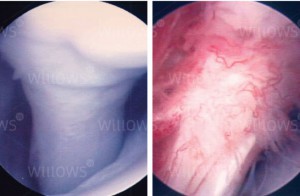

If you were to sustain a hit somewhere on your body with enough force, the point of impact would experience cell death and a micro-hemorrhage of torn capillaries. This trauma would then set up an inflammatory response in the body where vasodilation, clotting mechanisms, and white blood cells would be called upon to help the injured area. The problem is that this chemical chain of events doesn’t just “clean up” the injured area; unfortunately, it also eats/destroys the surrounding healthy tissue. So, if your injury is a small, one-time event, then it’s really no big deal, but, if it happens over and over again on a repetitive basis it becomes a real problem. The area begins to get inflamed; fibers from scar tissue cross bind to other healthy tissue and restrict freedom of motion. There is a loss of capillary beds in the tissue itself. Fluid from the inside of joint or tendon sheaths stops being produced and therefore, the sheaths lose their lubricating effect. Eventually, the healthy tissue is replaced with non-aligned, avascular tissue that has a reduced tensile strength. In other words re-injury and overuse of a joint experiencing tendonitis is likely to result in tendinosis; it’s the way the system is, unfortunately, designed.